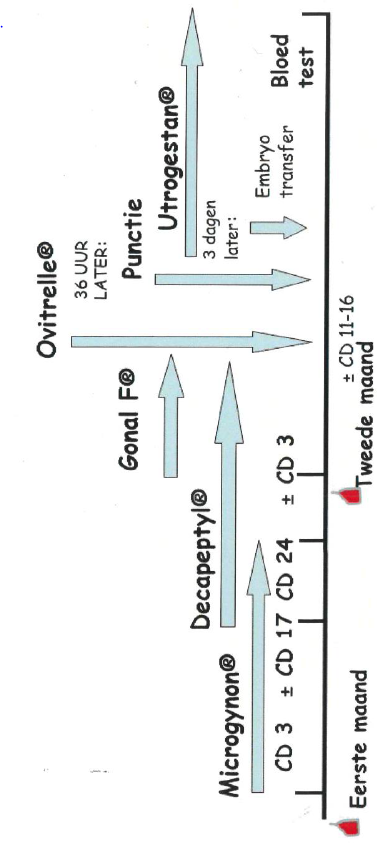

Het lange IVF- / ICSI-schema:

∆

zwangerschapstest

∆

∆

Uw IVF- / ICSI-behandeling volgens het lange schema strekt zich uit over twee maanden. U dient zich dit van tevoren goed te realiseren, in verband met planning van vakanties en werkzaamheden.

- Cyclusdag 1 (CD1): aanmelden

- Cyclusdag 2 of 3: eerste echo

- Cyclusdag 3 of 4: start pil (Microgynon 30®). De pil brengt de eierstokken tot rust. De pilstrip (21 tabletten) dient te worden afgemaakt. Bijna altijd zal er twee tot vier dagen na het beëindigen van de pilstrip een onttrekkingsbloeding optreden. Als er binnen een week geen bloeding optreedt, neemt u contact op met het IVF-centrum.

- Cyclusdag 17 of 18: start Decapeptyl® injecties. Eenmaal daags, één onderhuidse injectie. De Decapeptyl® injecties zijn enerzijds bedoeld om de eierstokken tot rust te brengen (versterking van het effect van de pil) en anderzijds om de natuurlijke eisprong te onderdrukken. Hierdoor wordt voorkomen dat de eiblaasjes al vanzelf zijn verdwenen voordat de punctie plaatsvindt.

Met de Decapeptyl® injecties gaat u door tot de eiblaasjes rijp zijn en de arts zegt dat u mag stoppen.

- Op de dag van de onttrekkingsbloeding na de pil neemt u opnieuw contact op met het IVF-centrum. U wordt ’s middags teruggebeld en krijgt een echo-afspraak. Als daar alles in orde is, start u nu daadwerkelijk met de stimulatie van de eierstok(ken) met Gonal-F ®. U gebruikt nu 2 injecties per dag, de Gonal-F ® en de Decapeptyl ®. Hiermee gaat u door totdat de eiblaasjes rijp zijn.

- Ook wanneer er geen echo-onderzoek na de onttrekkingsbloeding noodzakelijk is, neemt u wel contact op met het IVF-centrum op de eerste dag van de bloeding. U wordt ’s middags teruggebeld en krijgt instructies wanneer u start met de Gonal-F ® en met welke dosering. Tevens krijgt u dan een echo-afspraak na een aantal dagen stimuleren.